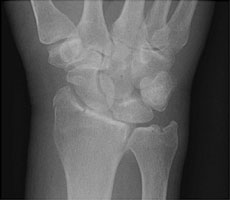

- Click on the image for a larger versionCPA radiograph of the wrist with scaphoid deviation. This also demonstrates the intraarticular involvement of this fracture.